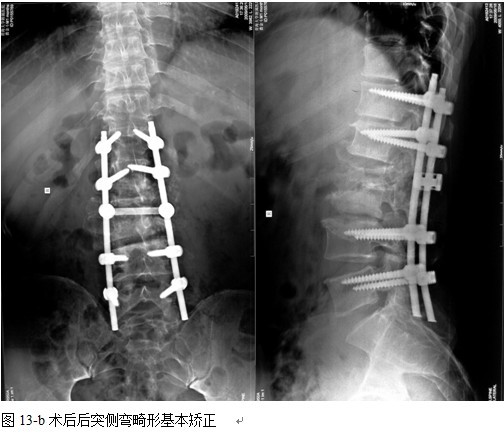

本组手术用时间3~4h , 平均3.5h 。术中出血300~500ml , 平均约350ml 。术后症状完全缓解,无神经功能障碍加重等并发症,1例营养差的老年患者伤口出现窦道,1例因肝功能差,术后未口服抗痨药,伤口出现窦道,经换药后二期愈合,其余病例伤口均一期愈合。马尾神经受损的患者术后基本恢复正常。术后一周后凸角平均 5.4°后凸畸形平均矫正90%以上, 最终后凸角平均8.3°,后凸角度平均丢失4.2°。随访3个月有87%(40/46)有骨痂形成,6个月91.3%(42/46)明显骨性愈合(见图),其余4例9-12个月内愈合,随访时间3-32个月,平均11个月,46例患者中2例在术后2个月和3个月时背部形成脓肿,换药后治愈。2例出院1月后并发结核性脑膜炎,治疗后好转。1例因椎弓根钉偏外,刺激神经根,5个月后从侧方脱出,疼痛加重,因前后路植骨完全愈合,取出后症状完全缓解。

中国学者金大地[22]等采用一期前路病灶清除植骨前路钢板固定治疗腰椎结核,平均18°的后凸畸形得以矫正,Mukhtar[23] AM等采用前路病灶清除植骨分期或同期后路固定治疗腰椎结核22例,术后后凸畸形矫正度数平均为27°。从我们的随访结果看,术后后凸畸形平均矫正度数为26.9°,后凸畸形平均矫正90%以上, 6个月-49个月后随访,后凸角度平均丢失4.2°。本术式也适用于结核所引起的弹性差的后凸畸形,对于病灶纤维化或骨化的非弹性后凸畸形,后路固定后,先行前路病灶、纤维化或骨化切除、松解,逐步刮除病灶、逐步撑开,达到畸形矫正和植骨的目的。